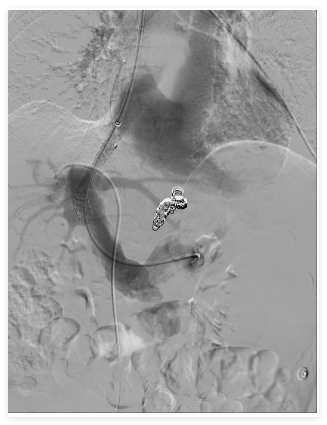

2.腹主动脉覆膜支架腔内隔绝术

①血管栓塞术:通过导管推入带纤毛弹簧圈,栓塞髂内动脉,防止内漏、出血等。

②血管内支架植入术:在扩张的动脉瘤内放置覆膜支架,隔绝异常瘤腔,防止破裂出血。

③血管扩张成形术:采用球囊扩张方式,使支架重叠处充分贴合,防止内漏发生。